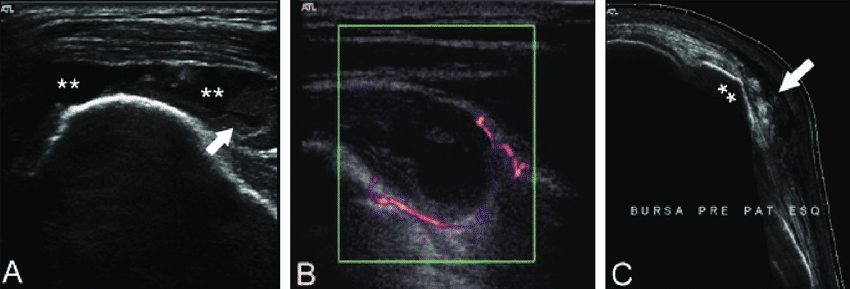

Na imagem abaixo é possível observar:

- (A) Bursite subacromial-subdeltóidea aguda, com líquido distendendo a bursa e espessamento parietal/sinovial (seta)

- (B) Sinovite com hiperemia ao Doppler

- (C) Bursite pré-patelar, em corte sagital, com bursa superficial à patela distendida por líquido hipoecogênico (seta).